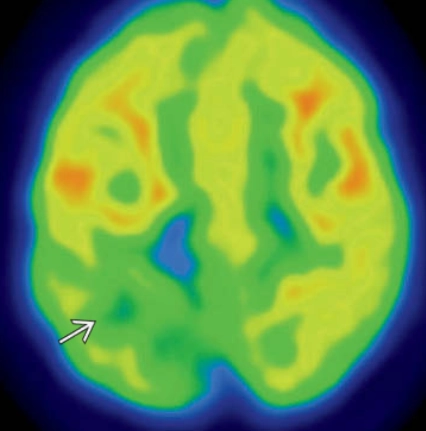

• Loạn sản vỏ não khu trú (Focal Cortical Dysplasias - FCD)

• Nhẵn não (Lissencephaly)- CT,MRI